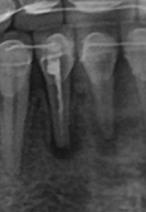

Проведена комиссионная судебно-медицинская экспертиза медицинских документов и осмотра пациента с целью оценки качества стоматологических услуг. Эксперты анализировали медицинские карты, рентгеновские снимки и данные КТ, сопоставляя их с действующими стандартами диагностики и лечения стоматологических заболеваний. В процессе исследования были изучены предоставленные планы лечения, примененные методики и используемые материалы. Особенное внимание уделялось оценке правильности выбора терапевтических и ортопедических решений, а также ведению медицинской документации. Работа включала анализ предыдущих заключений и врачебных комиссий. Экспертиза позволила установить соответствие или несоответствие оказанных услуг установленным нормам и протоколам, выявить потенциальные нарушения и их влияние на текущее стоматологическое состояние пациента, а также определить причинно-следственные связи посредством комплексного изучения всех предоставленных материалов.